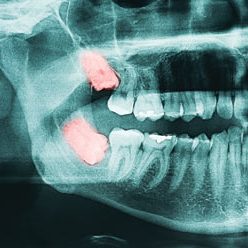

Wisdom Teeth

Wisdom teeth are the very last set of teeth that come out around the age of 16-25, some people also call it the third pair of molars. Not everyone develops wisdom teeth, most people that do have wisdom teeth do experience complications with them.